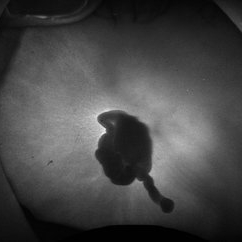

Fundus Autofluorescence of Closed Funnel Retinal Detachment

Fundus autofluorescence of a closed funnel retinal detachment; patient had previously undergone 360 degree retinectomy in attempt to re-attach retina for a chronic retinal detachment, which was unsuccessful.

Condition/keywords: Autoflourescence, Closed funnel RD, detachment